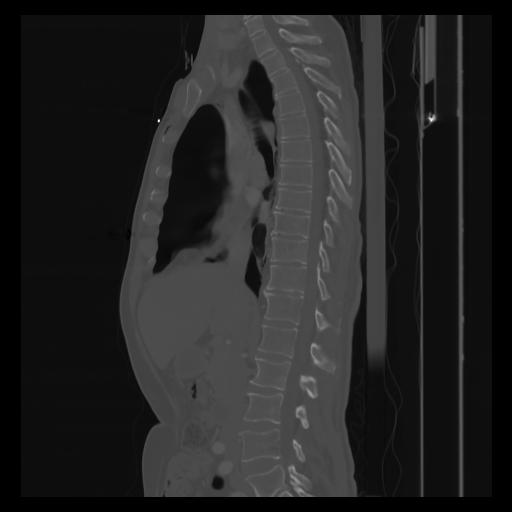

30 CUERPO,CE,Sagittal,3.000,CUERPO,Sagittal,